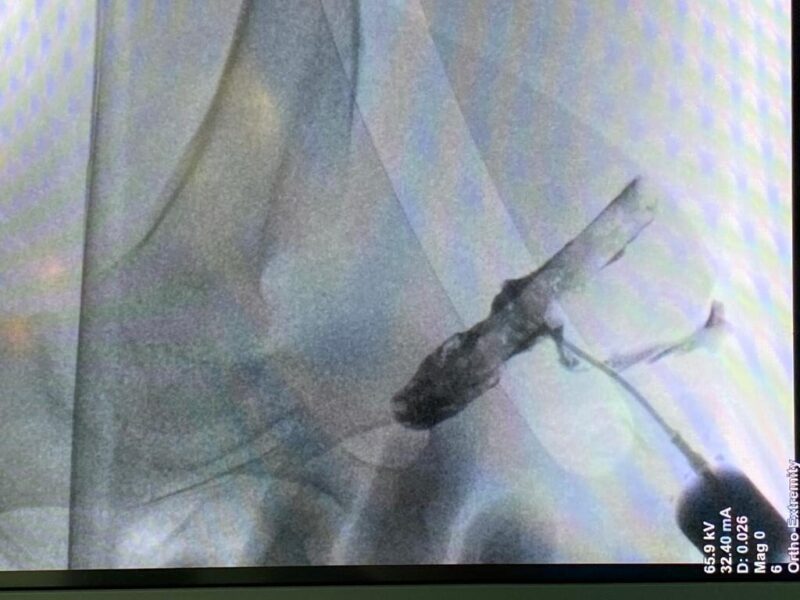

מכיוון שלא ידעו מה מקור הכאב, ערכו ברמב"ם מספר בדיקות, לרבות בדיקת אולטרסאונד עם חומר ניגוד, ובמהלכה נצפה העיפרון. "חקרנו כמה כיוונים, אך לבסוף הבחנו בפצע חדירה שהחל להזדהם באזור שרירי העכוז וחשדנו כי ההמצאות גוף זר בגוף הוא זה שגורם לזיהום ודלקות ולכאבים שמהם זה סובל", משחזר פרופ' אידלמן ומוסיף, "מעבר לכאב לא פשוט שאיתו ילד קטן צריך להתמודד, חשוב להבין שמדובר בחומר שמתעכל בגוף ועלול לסכן את הילד מכיוון שהוא מכיל חומר רעיל".

מרגע שהבינו את מקור הזיהום, הפעולה הייתה פשוטה יחסית – דרך פצע החדירה, נשלף הגוף הזר, אותו עיפרון שהיה בגופו של ש' חודשים ארוכים, ולאחר התאוששות קצרה ש' שוחרר לביתו כשצפויה לו החלמה מלאה.